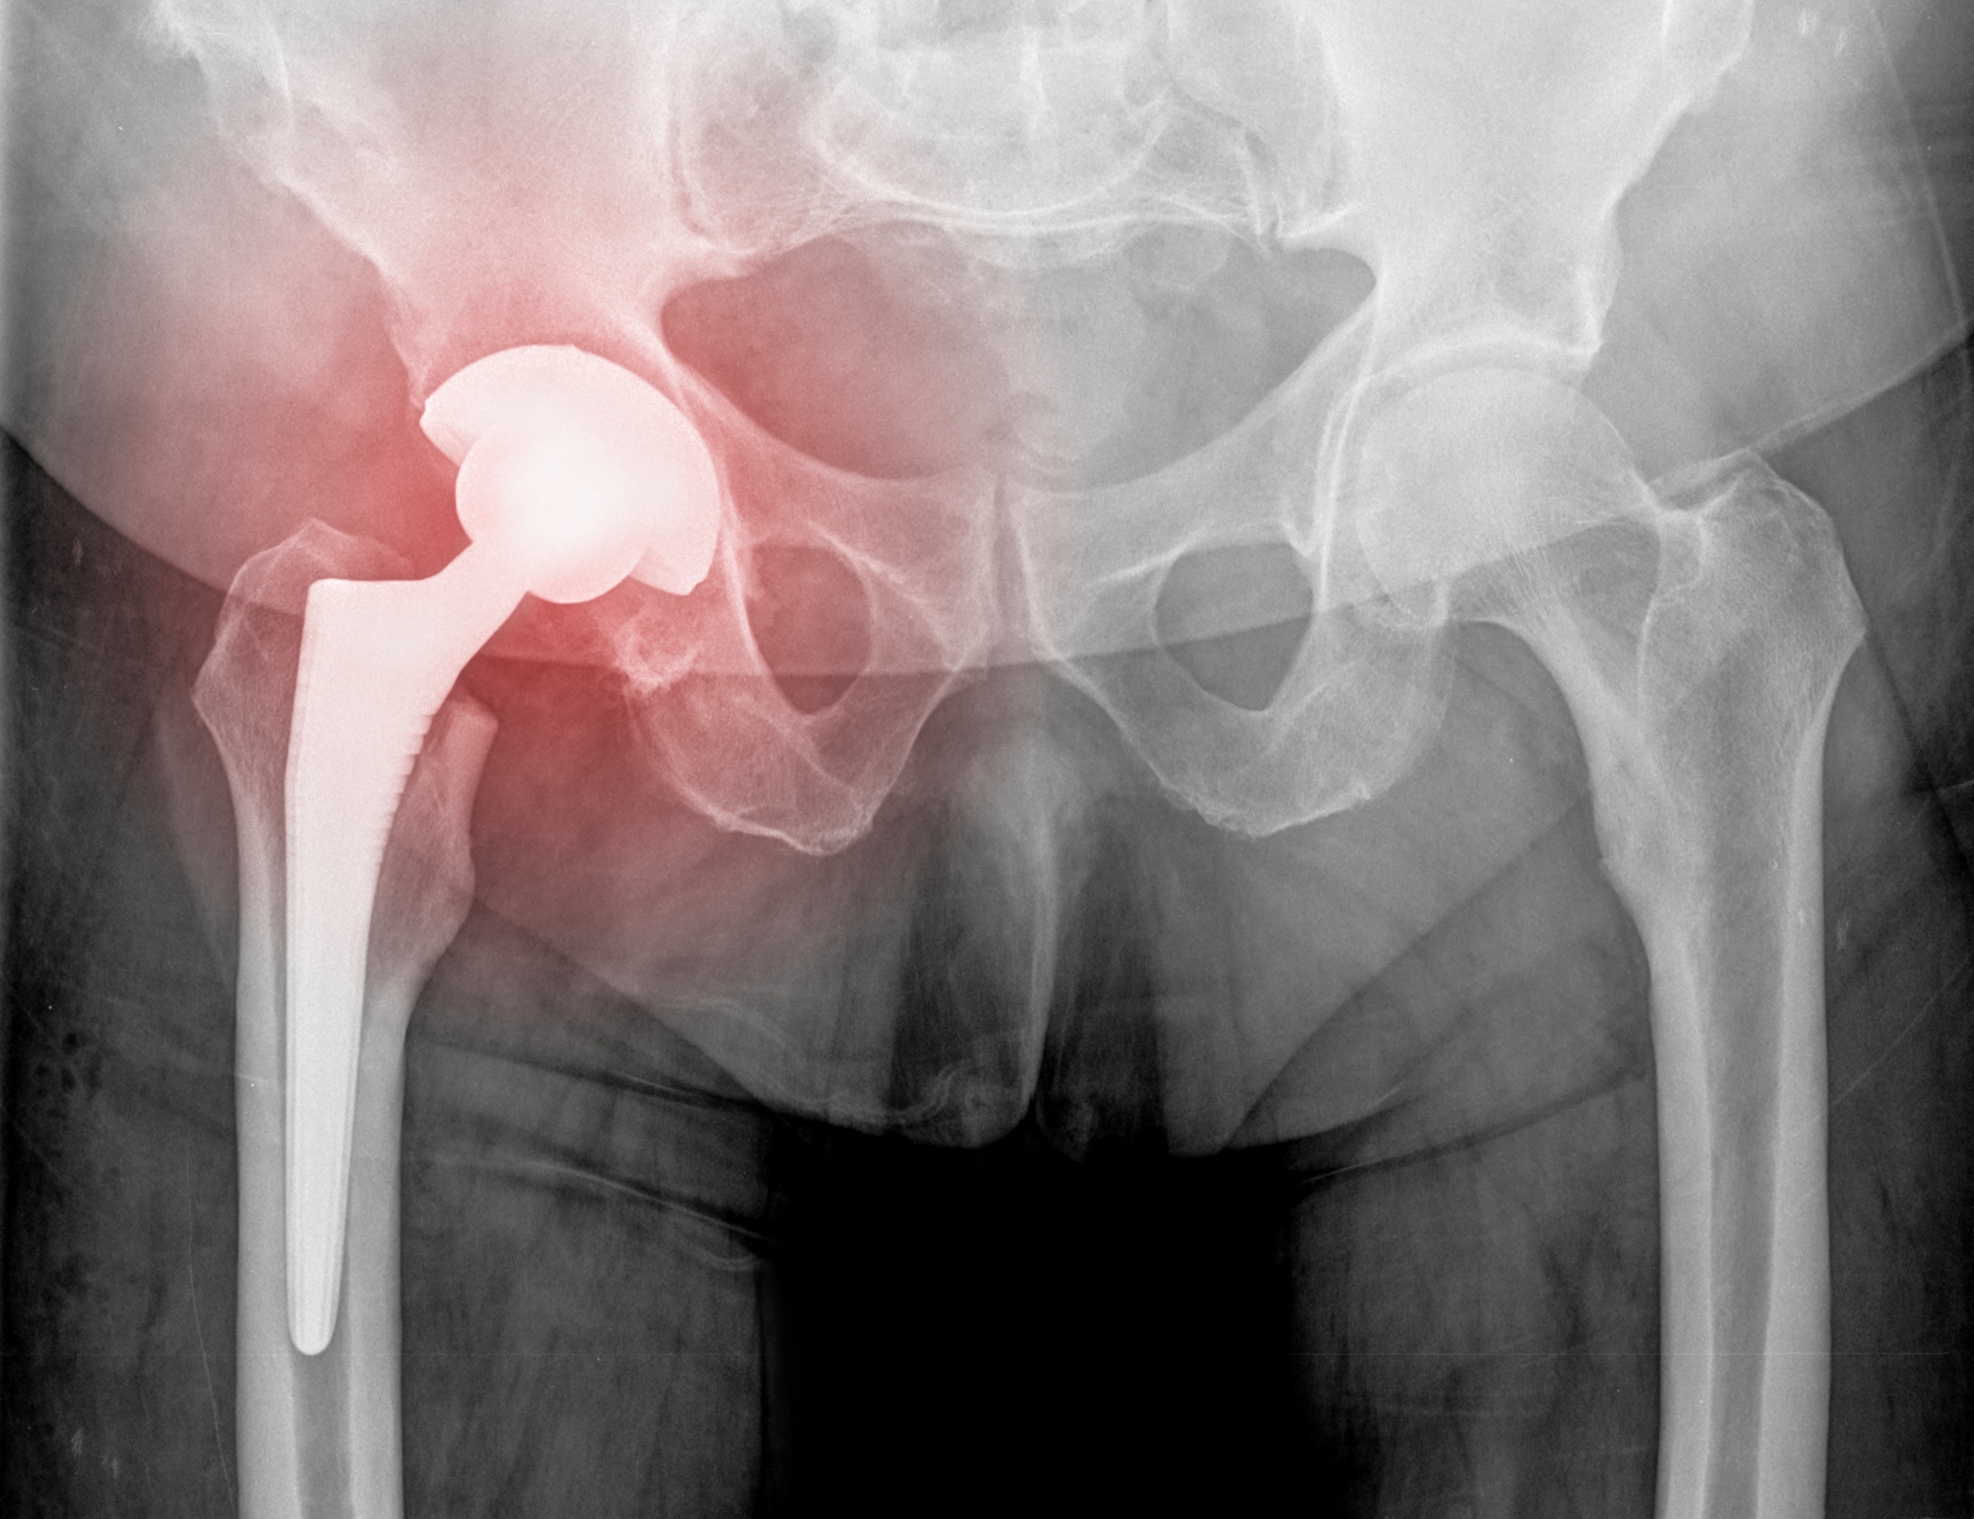

Včasih pa so vzrok za bolečine v kolku nepravilno oblikovane kosti ali pa sčasoma pride do tako velike obrabe, da se operativnemu posegu ne moremo izogniti. Tudi v teh primerih bosta fizioterapija in kinezioterapija v rehabilitaciji uspešno pripomogli k povrnitvi funkcije in življenju z manj bolečinami.

Artritis je izraz za vnetje sklepov in obsklepnih struktur. Poznamo veliko različnih vrst, med njimi sta najbolj pogosta osteoartritis in revmatoidni artritis, med revmatske bolezni pa spadata tudi putika in fibromialgija. Osteoartritis (OA) kolka je zelo pogost problem zahodne družbe. Prizadene kar do 25 % populacije starejše od 55 let, pogosteje zbolijo ženske, k nastanku pa ob staranju pripomorejo tudi genetski dejavniki in življenjski slog.

Pri OA gre za progresivno obrabo hrustanca, posledično pa pride do stika kosti ob kost kar povzroči spremembe na kostnem sistemu. Seveda pa ena sprememba vpliva na drugo in so ob tem prizadete tudi mehko-tkivne strukture kolčnega sklepa.

Osteoartritis je degenerativno stanje, ki se bo, brez primerne fizioterapevtske rehabilitacije, progresivno slabšalo in povročalo vedno hujše bolečine in omejitve gibanja.